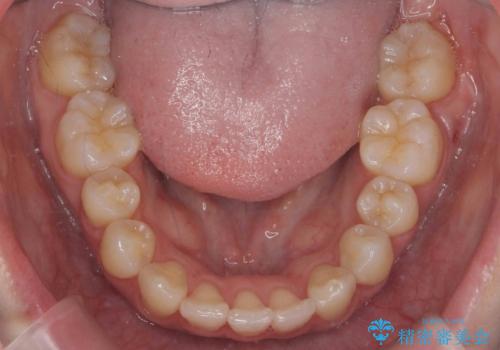

下顎がとても小さく後方位であるため、オトガイの閉口時のシワは完全になくすことは難しかったですが、前歯も大きく下がり満足していただきました。

矯正治療は審美的な側面を持っておりますが、小さすぎる下の顎に口元を無理やりあわせるのも、歯の移動量が大きすぎて適切な治療とは言えないと思います。健康を損なう美容整形とは違うからです。前歯については、適度に下げる量をコントロールすることも大事です。